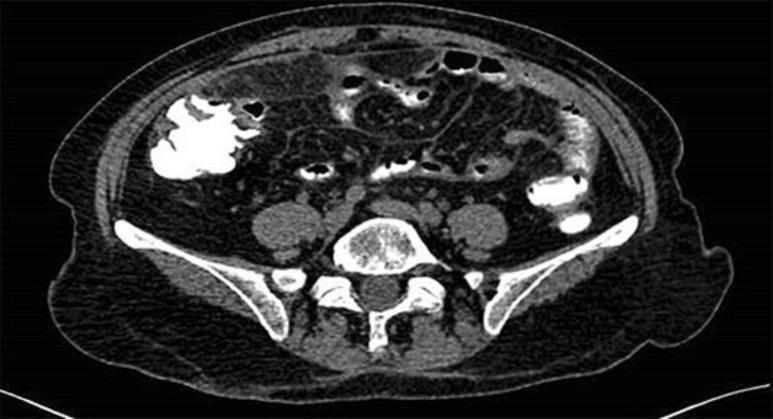

A 53-year-old woman was diagnosed with advanced gastric carcinoma, with extensive omental caking and several peritoneal implants measuring 2 cm at the largest diameter. The patient received mFOLFOX6 for 6 months with excellent clinical and radiographic response. She was then submitted to a D2 total gastrectomy followed by CRS and HIPEC with mitomycin. The final pathology report showed a focal adenocarcinoma in the stomach measuring 0.4 mm with no residual tumor in the peritoneum (ypT1ypN0). The patient has been well and disease free for more than 4 years.

一名53岁女性被诊断为晚期胃癌,伴有广泛的大网膜结块和多处腹膜转移灶,最大直径为2 cm。患者接受mFOLFOX6治疗6个月,临床和影像学反应良好。随后她接受了D2全胃切除术,接着行CRS和丝裂霉素腹腔内热化疗。最终病理报告显示胃内有一个0.4 mm的局灶性腺癌,腹膜无残留肿瘤(ypT1ypN0)。该患者已健康无病生存4年多。